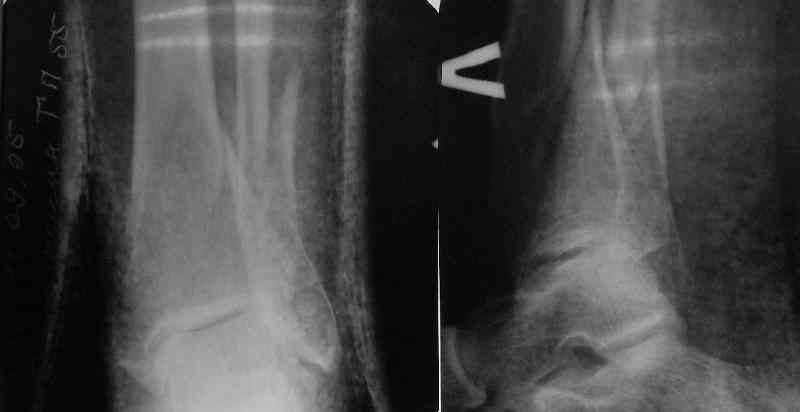

In delayed cases acute length restoration performed only in the tibia may leave the fibula shortened thus change the mortise. So it is reasonable to restore length of both bones simultaneously by distractor and fix the fibula not with open reduction and plating but just by a single perQ screw. Example attached.